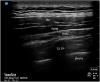

Continuous erector spinae plane block for acute pain control in chest wall reconstruction of extensive traumatic degloving injury

Keywords: Acute pain; Breast pain; Erector spinae block; Regional anesthesia and trauma.